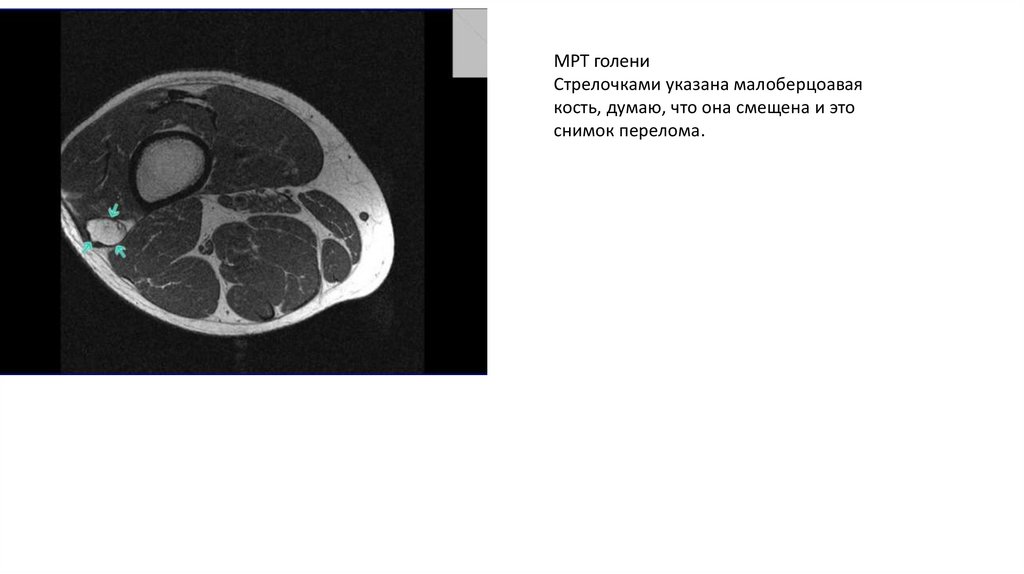

МРТ голени

Стрелочками указана малоберцоавая

кость, думаю, что она смещена и это

снимок перелома.